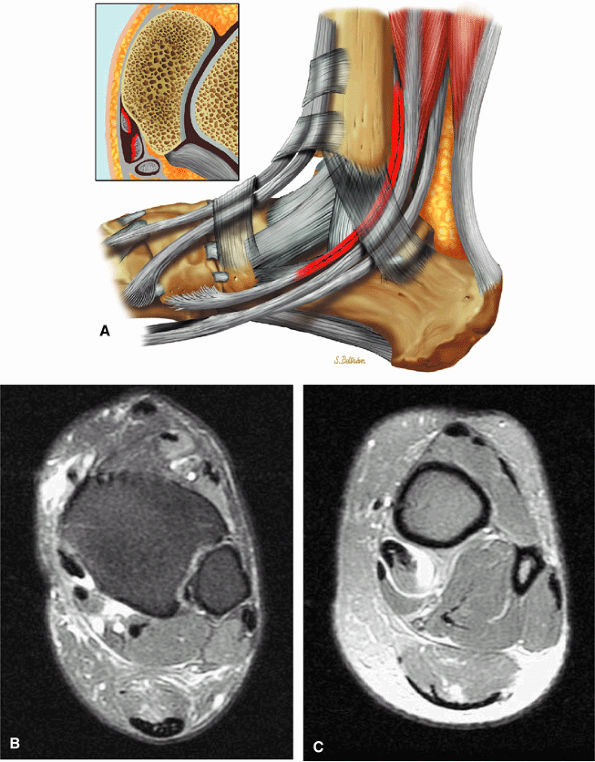

Type 2: There are thin or attenuated sections of the tendon at the level of the medial malleolus53 with variable intratendinous signal change (Fig. 5.132). Subtendons may occur associated with mixed areas of atrophic and hypertrophic tendon segment (Fig. 5.133).

FIGURE 5.132 ● (A) Type 2 tibialis posterior tear with the generation of two subtendons. Lateral color graphic with axial inset. (B, C) Attenuated tibialis posterior tendon at the level of the medial malleolus with hypertrophy of the more proximal tibialis posterior associated with tendinous fiber retraction. Axial FS PD FSE images.